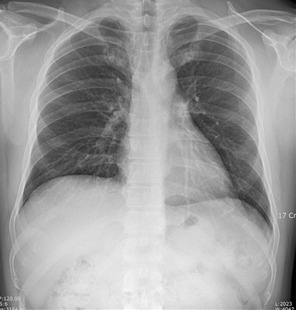

- 흉부 X선 검사: 가장 기본적인 검사로, 흉부에 X선을 투과시켜 폐에 있는 이상 소견을 확인합니다. 그러나 초기 폐암은 X선에서 발견되지 않을 수 있어 추가 검사가 필요할 수 있습니다.